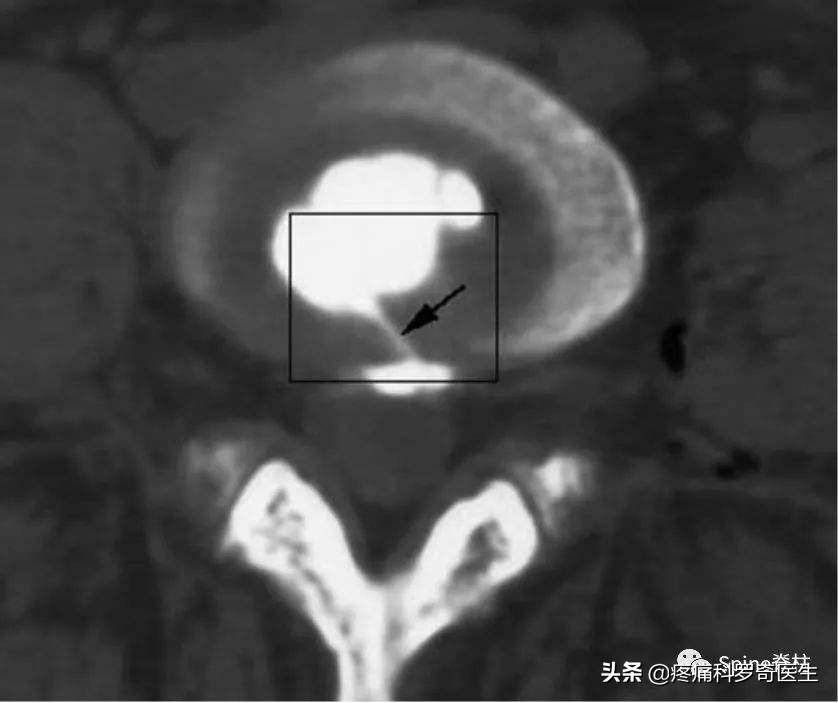

箭头所示的地方就是椎间盘的裂缝

啥叫盘源性腰痛呢?腰椎间盘里面本来是没有神经分布的,但是腰椎间盘外层的壳有小的裂缝,有一些小的神经张进去了,这种神经叫窦椎神经,椎间盘内有炎症灶持续的刺激这种神经,所以你会觉得痛。当你休息一段时间、或者做理疗了,这个炎症灶就轻一点,症状就消失了,当你劳累了、变天了,这个炎症灶就又来了。这也就解释了,你这个腰痛,为什么反反复复,就是不好。